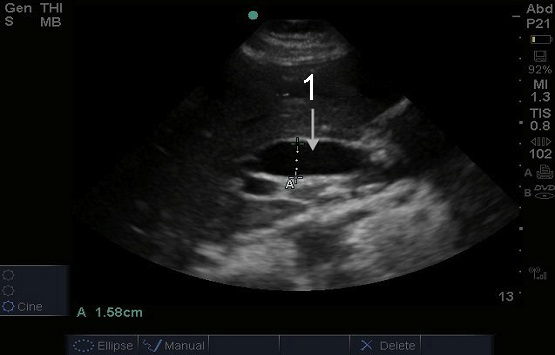

胆嚢サジタル拡張総管像

拡張共通ダクト